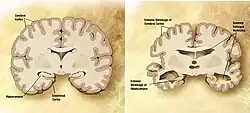

![]() Et diagram over en normal hjerne (venstre) og en Alzheimer-patients hjerne (højre)  | |

Alzheimers sygdom er kendetegnet ved et tab af neuroner og synapser i hjernebarken og visse subkortikale regioner. Dette tab fører til atrofi i de pågældende regioner med degeneration i tindinge- og isselappen samt dele af frontallappen og gyrus cinguli.[53] Der sker ligeledes degeneration i hjernestammekerner såsom locus coeruleus.[71] Studier har ved brug af MR-scanning og positronemissionstomografi kunnet dokumentere, at visse hjerneregioner hos mennesker med AD skrumper efterhånden, som de går fra mild forringelse af kognitive evner og til Alzheimers sygdom sammenlignet med lignende billeder fra sunde ældre mennesker.[72][73]

Ved mikroskopi af hjerner hos patienter med AD ses tydeligt både amyloidplak og neurofibrillære sammenfiltringer.[74] Plakken fremstår som tætte, hovedsageligt uopløselige, depoter af beta-amyloid peptid og cellemateriale uden for og omkring neuroner. Neurofibrillære sammenfiltringer er ophobninger af det mikrotubuli-associerede protein tau, som er blevet hyperfosforyleret og samles inde i selve cellerne. Selv om mange ældre mennesker udvikler plak og sammenfiltringer som en konsekvens af naturlig aldring, har hjerner hos mennesker med AD et større antal af disse i specifikke hjerneregioner som i tindingelappen.[75] Lewy-legemer, der ellers normalt associeres med Parkinsons sygdom, kan somme tider ses i hjernen hos mennesker med AD.[76]